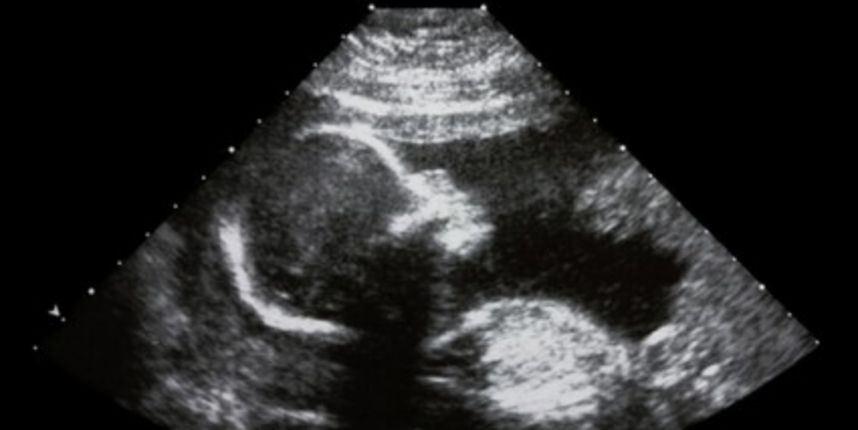

Pilula koja se pripisuje majkama koje očekuju djevojčice s rijetkim genetskim poremećajem koje se naziva kongenitalna adrenalna hiperplazija (CAH) izazvala je žestoke reakcije. Naime, pilula bi ujedno mogla i značajno smanjiti mogućnosti da novorođena djevojčica postane lezbijka, prenosi Daily Mail.

Kongenitalna adrenalna hiperplazija uzrokuje nagomilavanje muških hormona, zbog čega je kod ženske djece isprva teško otkriti kojeg su spola. Iako se njihovi unutrašnji organi razvijaju normalno, razvijaju se i abnormalne vanjske karakteristike kao što je dubok glas i pretjerana dlakavost.